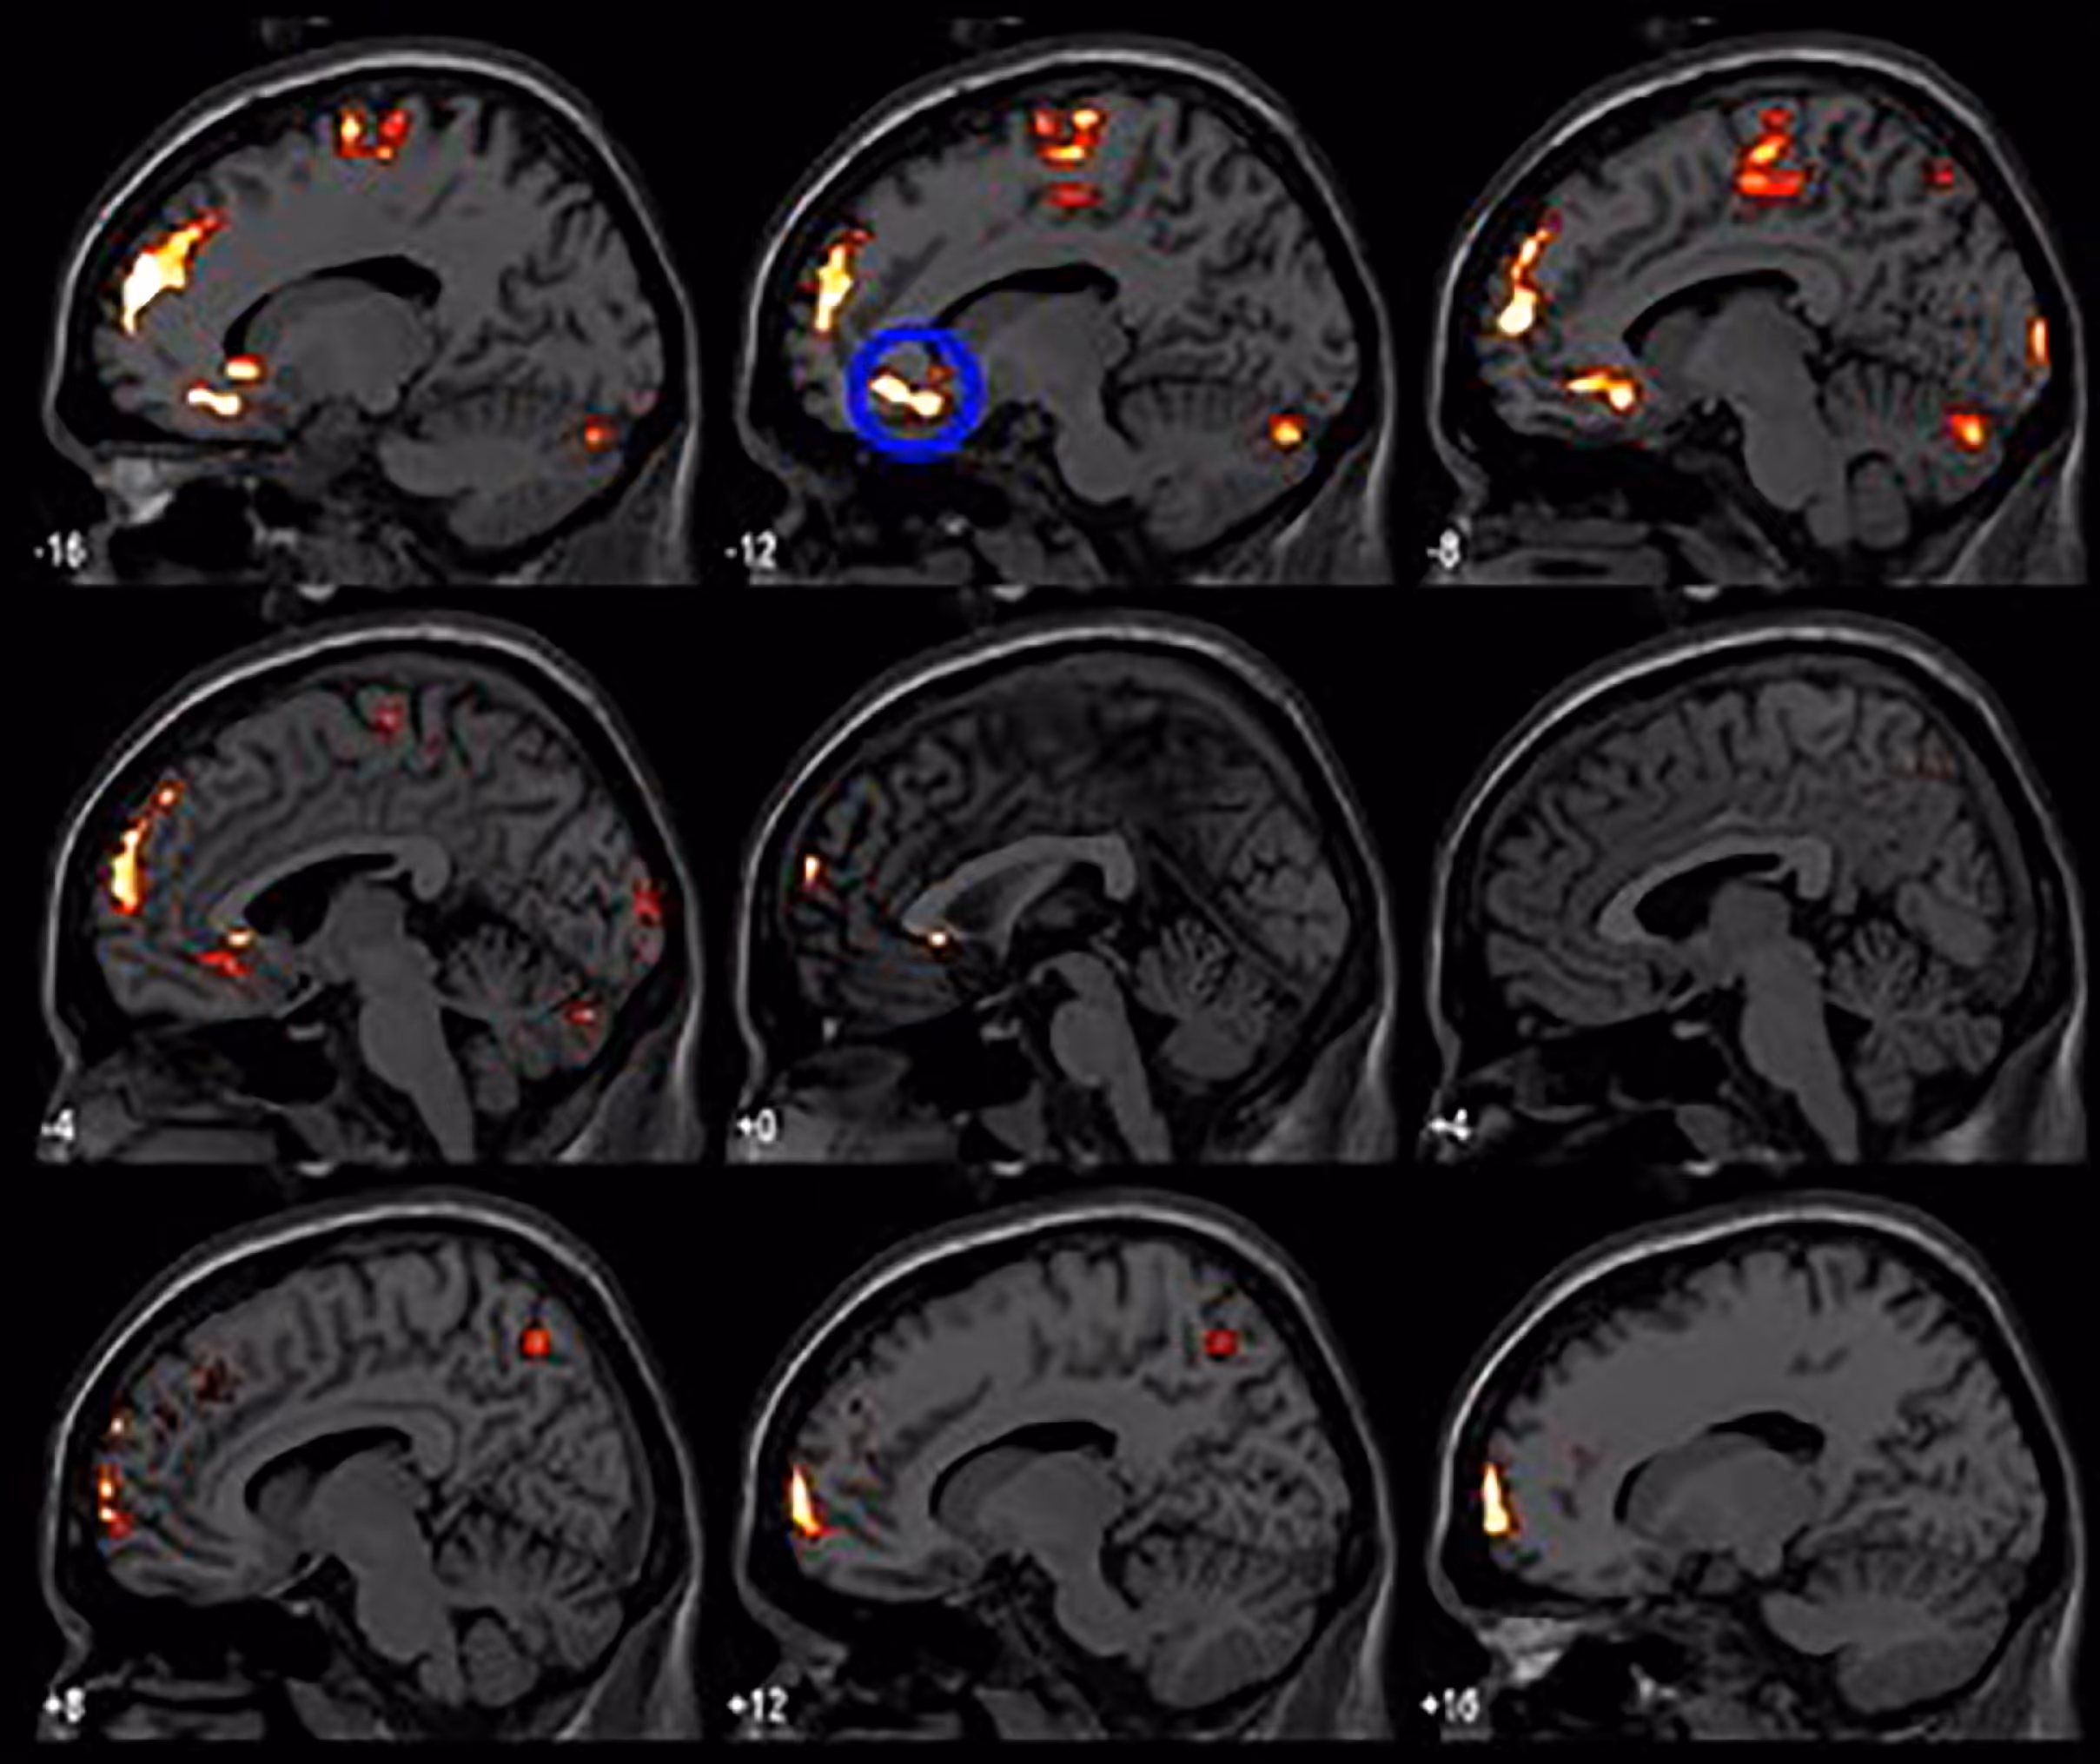

In the context of migraine and chronic headache, TMS works by modulating neural circuits involved in pain processing, cortical excitability, and abnormal brain activity patterns that drive recurrent attacks. Research has shown that patients with migraine often exhibit heightened cortical hyperexcitability, a state in which the brain's pain networks are abnormally sensitive to triggers. TMS can help lower this sensitivity and reduce the frequency and intensity of attacks without adding another drug to your regimen.